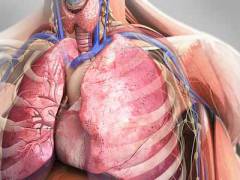

Анатомия грудной клетки

Грудная клетка включает костный каркас и мышечную структуру. В грудной полости расположены органы дыхательной, сердечно-сосудистой, пищеварительной и эндокринной систем, а также крупные кровеносные и лимфатические сосуды.

Органы и структуры грудной клетки

В процессе эволюции человеческий скелет обеспечил защиту жизненно важных органов. Головной мозг находится в спинномозговой жидкости внутри черепа, половые органы защищены костями таза, а органы дыхания и сердечно-сосудистой системы располагаются в грудной клетке.

Грудная клетка включает:

- легкие;

- трахею;

- главные бронхи;

- сердце;

- аорту и её ветви;

- верхнюю и нижнюю полую вены;

- пищевод;

- тимус (вилочковая железа);

- общий лимфатический проток;

- лимфатические узлы;

- крупные нервы (блуждающие, диафрагмальные, симпатический ствол) и другие.